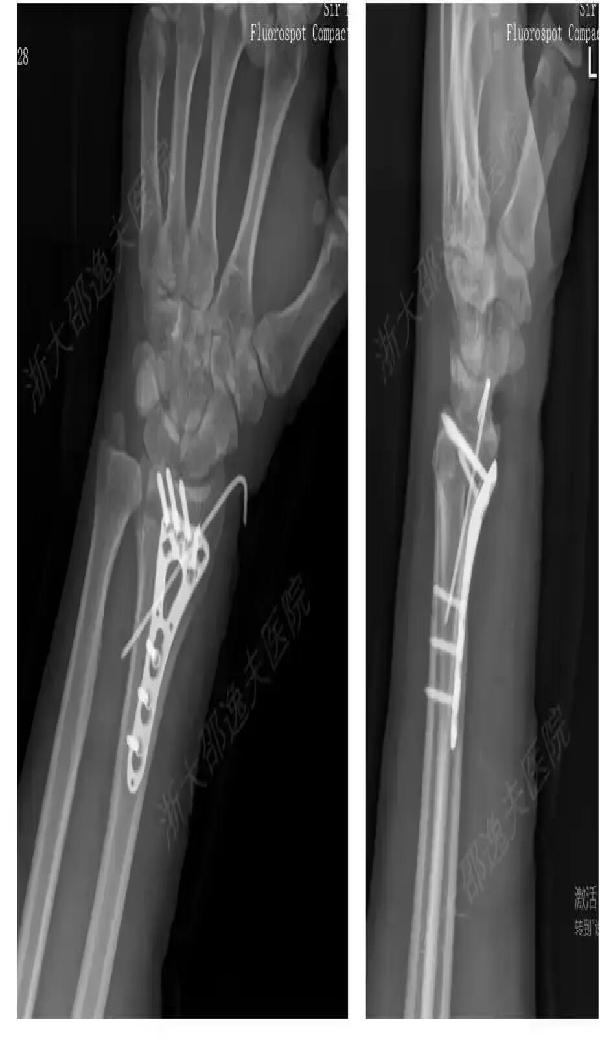

一位年轻工人因外伤导致腕部桡骨远端粉碎性骨折,按照传统治疗方案,需大切口植入钢板螺钉,创伤大且存在肌腱粘连或神经损伤风险,术后一年还需二次手术取出。而应用 “骨 02” 黏合技术,医生仅通过一个 2 至 3 厘米的微创切口注入骨胶水,短短 3 分钟内就完成了粉碎骨块的精准黏合与固定。术后 3 个月随访显示,患者骨折愈合良好,无并发症,腕关节功能完全恢复。